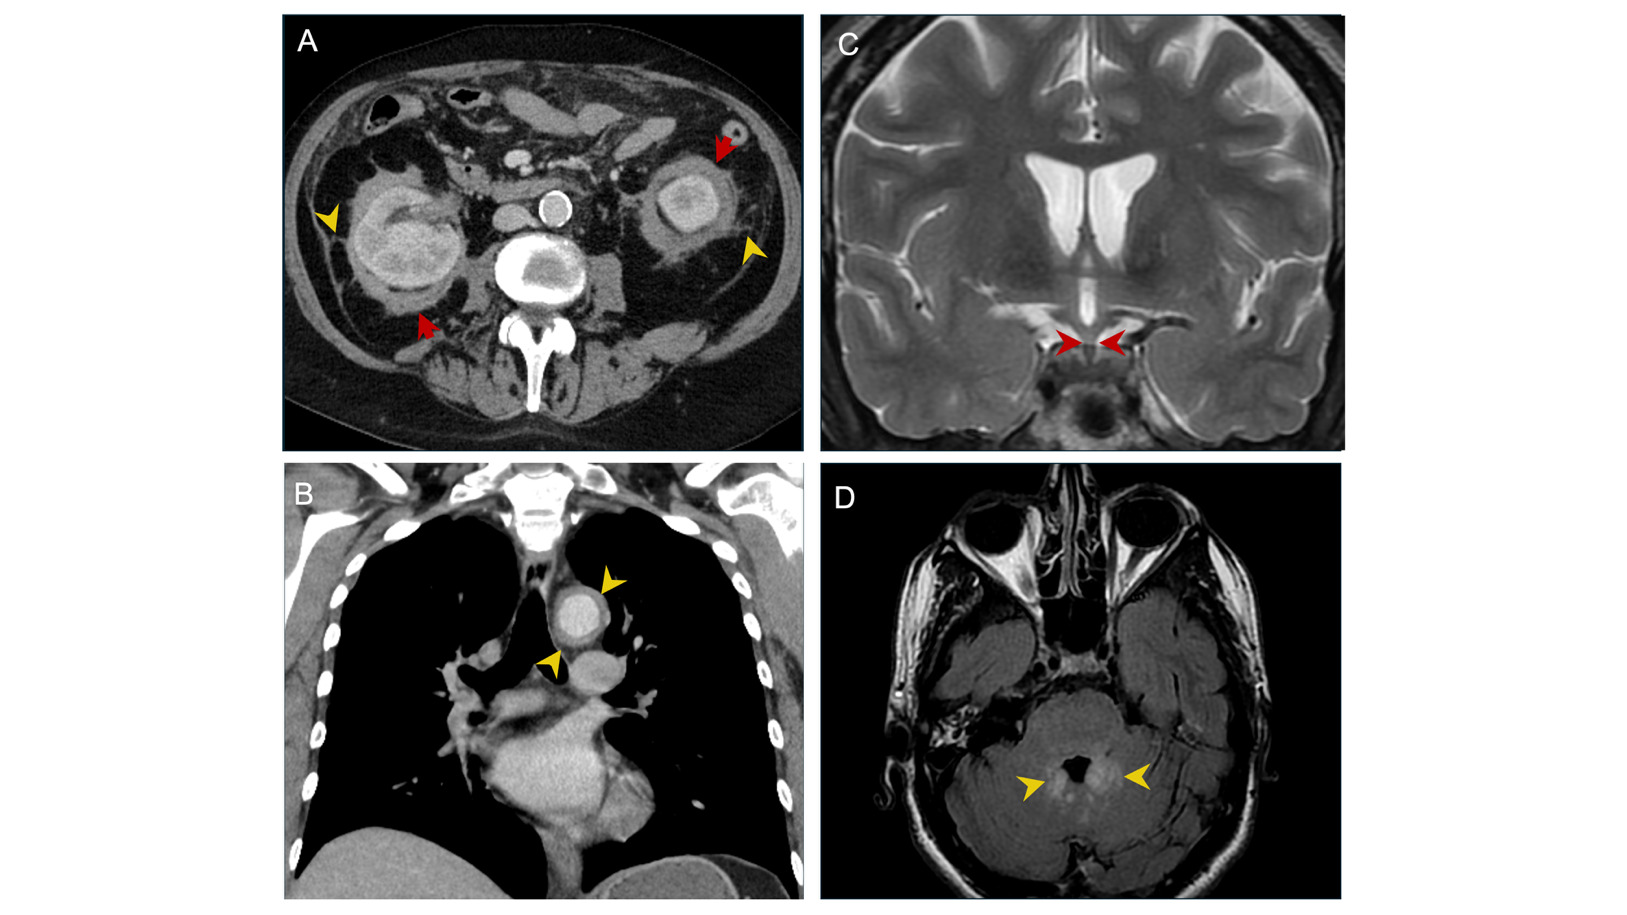

Of the 11 patients, nine were subjected to FDG PET-CT imaging. The most frequent finding was skeletal involvement (n=7), typically as sclerotic lesions or diffuse long bone infiltration. Renal and perinephric involvement was also common (n=6), including soft tissue infiltration and perirenal septal thickening consistent with the ‘hairy kidney sign’ (Figure 2A) and retroperitoneal fibrosis. Pericardial abnormalities, including effusion, thickening, or mass, were noted in three patients. One patient showed the classic ‘coated aorta sign,’ characterized by circumferential aortic infiltration (Figure 2B). Neurological findings were also observed, including a thickened pituitary infundibulum (Figure 2C) and bilateral cerebellar dentate hyperintensities (Figure 2D). Other frequently involved areas included the lymph nodes (n=3) and lungs (n=3). Less common FDG PET-CT findings included adrenal gland involvement (n=1), testicular FDG uptake (n=1), and gastric pylorus activity (n=1).